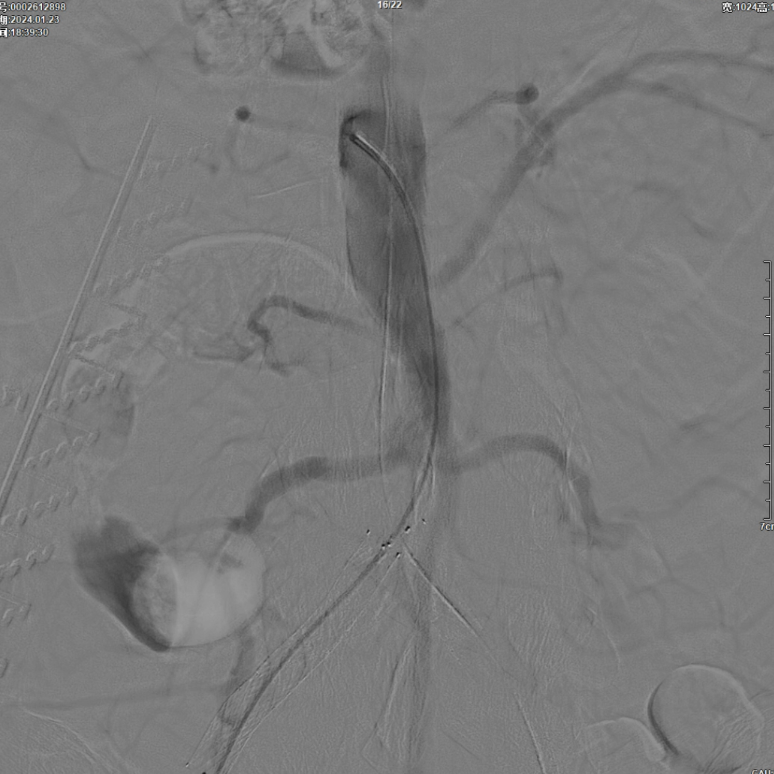

右侧髂外动脉存在残存狭窄,因该部位无原有裸支架覆盖,为节省治疗费用,选择植入1枚直径8mm的裸支架,并采用8mm球囊进行后扩张。

即时效果:造影显示腹主动脉、双侧髂总/髂外动脉及股动脉通畅。

术后对患者应用利伐沙班进行抗凝治疗,同时给予阿司匹林抗血小板治疗,期望右侧股动脉闭塞病变能通过自身纤溶作用实现再通。

3个月复查:右侧股动脉完全再通,无残存狭窄;CTA显示腹主动脉、双侧髂动脉及远端股动脉通畅,双侧ABI>1.0;左侧髂动脉开口打开不全(推测与对吻球囊直径选择有关,原用8mm,若选10mm可能避免),因患者无症状,暂密切随访,远期若再狭窄可采用10mm球囊扩张。